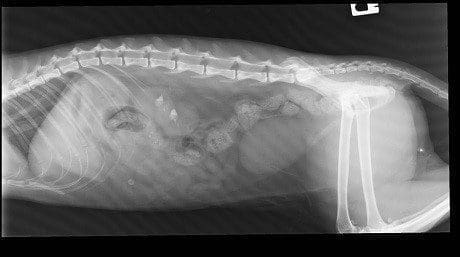

Lateral and DV abdominal radiographs were obtained which confirmed that Lucy has fairly sizeable bilateral renoliths (Figure 2). It would seem likely that these are calcium oxalate given previous history and presence of hypercalcaemia. A Bates body which is thought to occur due to fat necrosis was also noted incidentally.

Figure 2. A right lateral abdominal radiograph. Radiopaque renoliths are visible within the collecting system of both kidneys (red arrows). The incidental fat necrosis appears as a round radiopaque area within the ventral abdomen (yellow arrow).